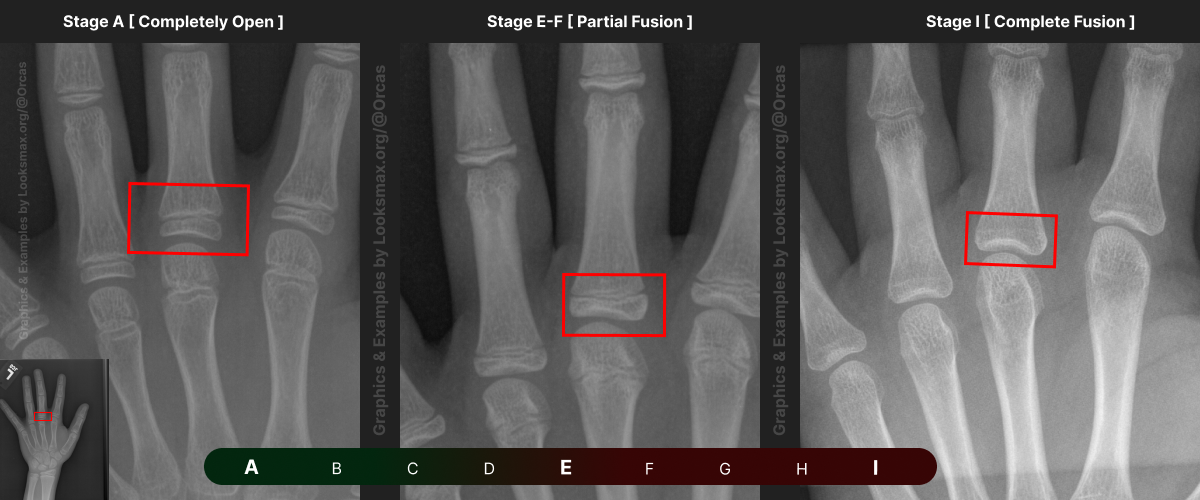

I added references for stages A (Completely unfused), E-F (Partial fusion, basically late stages of puberty), and I (Complete Fusion)

You will have to eyeball this now using your own xrays, I’ve given three examples and some wiggle-room for letters using a reference bar (green-red) below the image, write down your estimated guesses in a text file until you finish all 13 bones.

Don’t doubt yourself, eyeballing isn’t perfect but it still works well, just choose & continue.

Ex.

“My Radius looks more fused than the image from E-F, but its not as fused as I, it’s closer to the 2nd picture though, so I’ll rate it G” And continue

Bonetype: 3rd Proximal Phalanx

Bonetype: 5th Proximal Phalanx